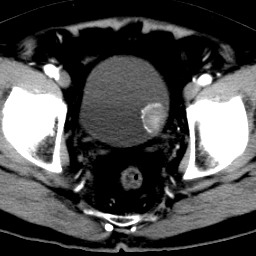

男,79岁,无痛性肉眼血尿1周。

由膀胱左侧后壁向内突出一圆形肿物,边缘光滑伴钙化,内密度均匀。支持考虑:膀胱癌!

蛋壳样钙化------应该是良性病变的影像表现。期待病理。

膀胱ca并肿瘤表面钙质沉积

膀胱左后侧壁可见软组织块影宊向腔内,边缘钙化,考虑膀胱占位,癌可能性大。

术后病理示:膀胱乳头状癌。